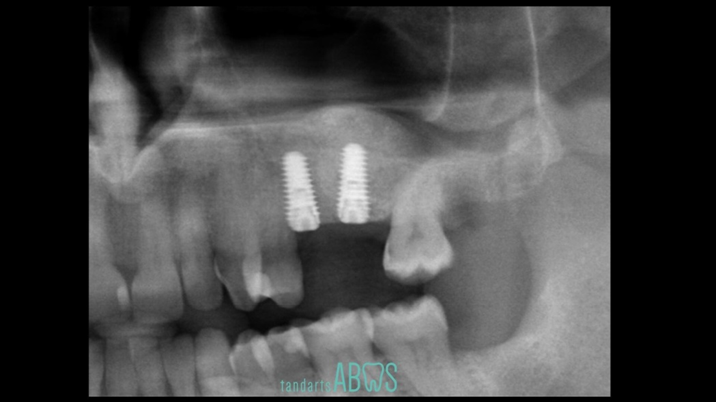

“AnyRidge KnifeThread achieves excellent stability in regenerated bone & even in only 3mm bone height!”

Clinical case: Installation of dental implants in complicated anatomic conditions using crest lifting methods

- Courtesy of Dr.Alexander Lysov, Russia -